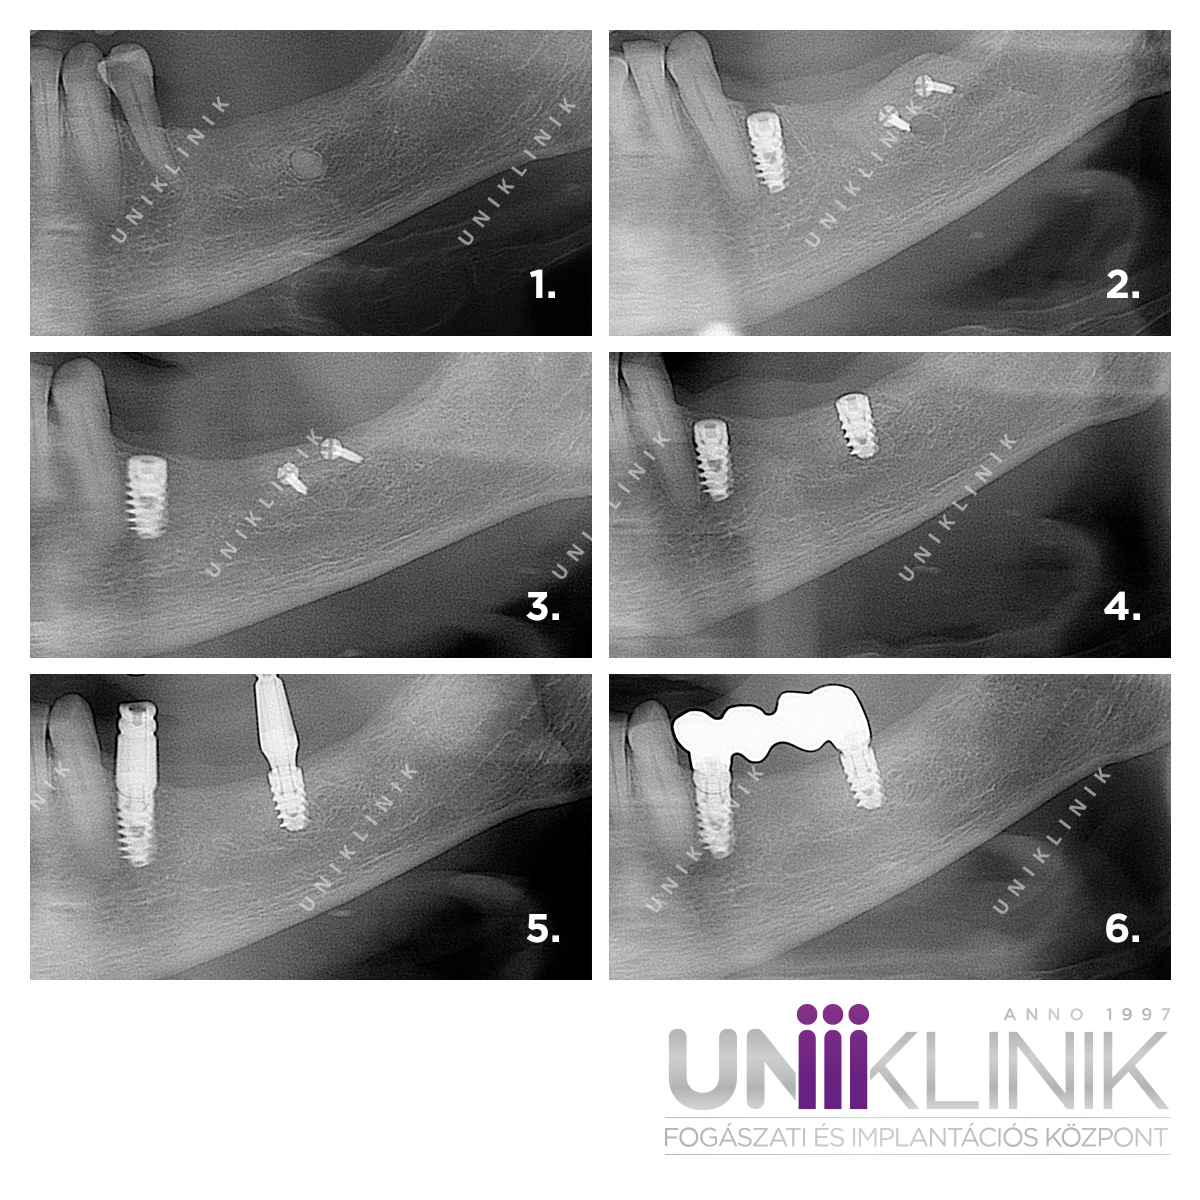

Csontpótló csontblokk műtét fogászati implantációt megelőzően

Az alábbi kollázson egy nagyobb csonthiány esetén alkalmazott csontblokk műtét képei láthatóak. A csontátültetés során az állkapocs hátsó részéről egy csontblokkot ültetett át Dr. Záhonyi Balázs, dentoalveolaris szájsebész szakorvos az implantálni kívánt területre, amit titáncsavarokkal rögzített.

A csontblokk műtétet követően 3-6 hónap gyógyulási idő szükséges a csontosodáshoz. Ezután történhet meg az implantátum beültetése a csontpótolt területre, majd további 4-6 hónap gyógyulási idő után készülhet el a fogpótlás az implantátumra, mely ebben az esetben egy háromtagú fogászati híd volt két fogimplantátumon.